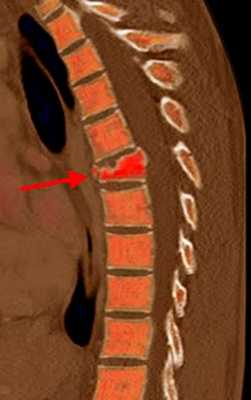

(Слева) КТ, сагиттальный срез: оскольчатый взрывной перелом тела L4 позвонка со смещением фрагмента кпереди и выраженным смещением одного из фрагментов кзади.

(Справа) На Т1 -ВИ отмечается снижение интенсивности сигнала тела L4 позвонка на фоне его перелома. Смещенные кзади фрагменты сдавливают вентральную поверхность дурального мешка, имеет место значительных размеров эпидуральная гематома. Таким образом, выраженная компрессия дурального мешка связана со смещением фрагментов в спинномозговой канал и эпидуральной гематомой.